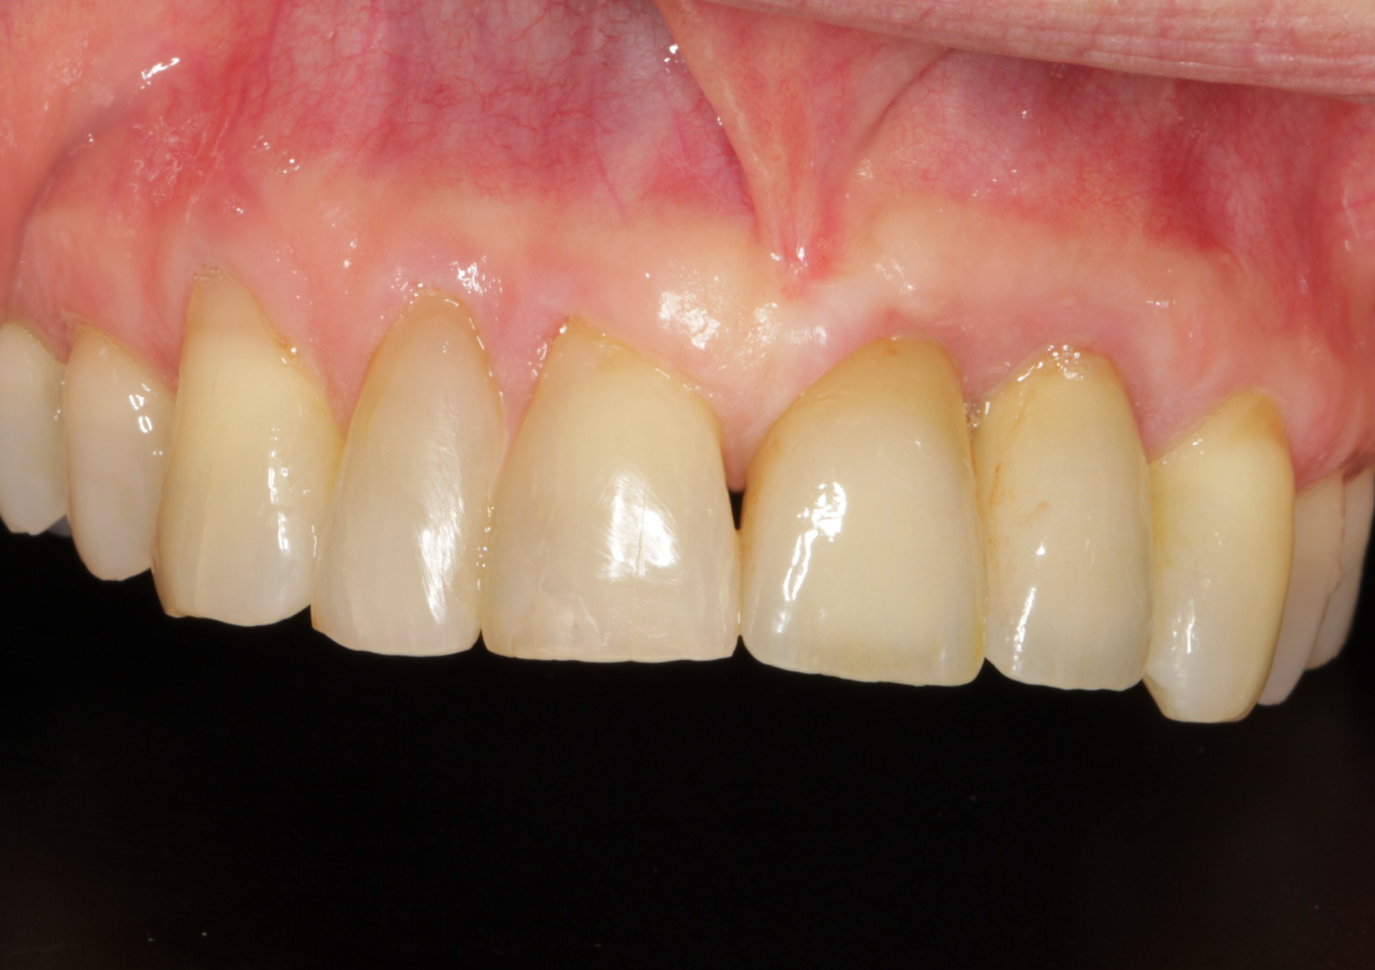

Figure 3.

Final restoration (a customized CoCr structure from ARC solutions, layered with ceramic) at time of delivery, showing healthy peri-implant tissue.